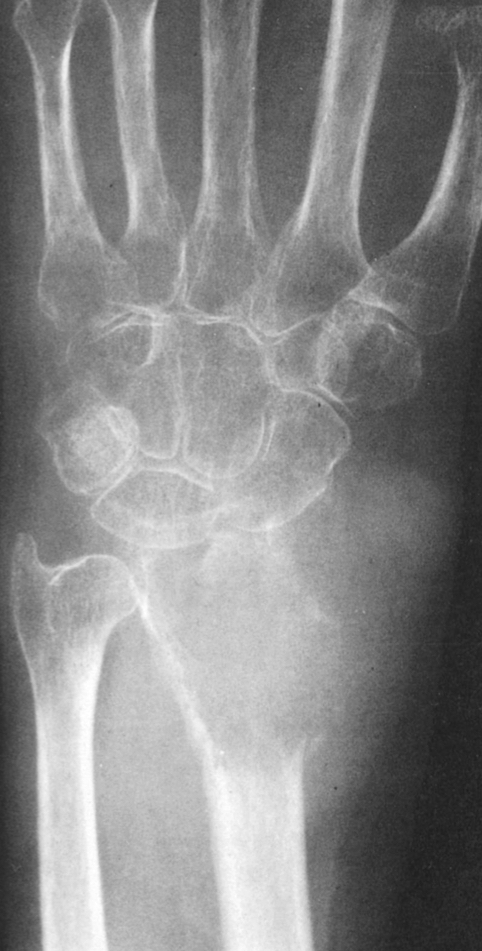

describe this. what is this?

distal radius

extends into subchondral region

diminished bone density

appears aggressive

malignant GCT